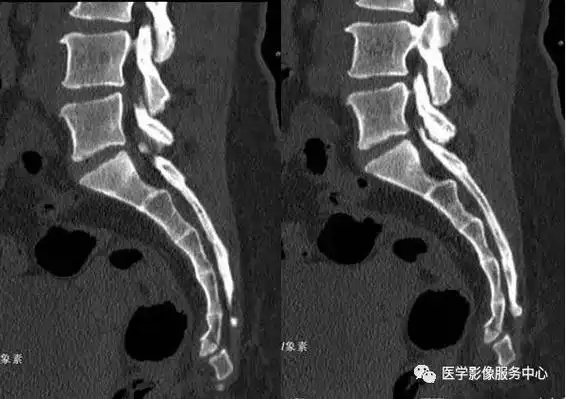

男性患者47岁因腰骶不适摄片

【读片】骶尾椎ct [病例帖]